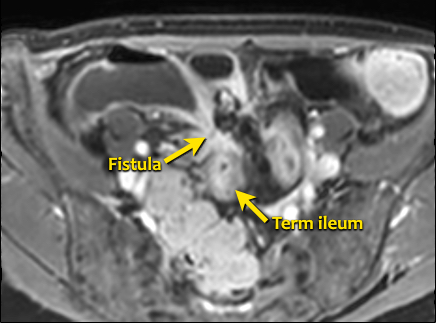

Rò

Đường xoang và đường rò là các biến chứng thường gặp ở bệnh nhân mắc bệnh Crohn.

Cả hai đều ngấm thuốc rõ rệt trên chuỗi xung T1W sau tiêm gadolinium.

Đường rò có thể biểu hiện dưới dạng cấu trúc phân lớp kiểu ‘đường ray tàu hỏa’ hoặc như một cấu trúc tuyến tính ngấm thuốc.

Đường rò có thể đi từ quai ruột này sang quai ruột khác, đến một tạng rỗng khác hoặc ra da.